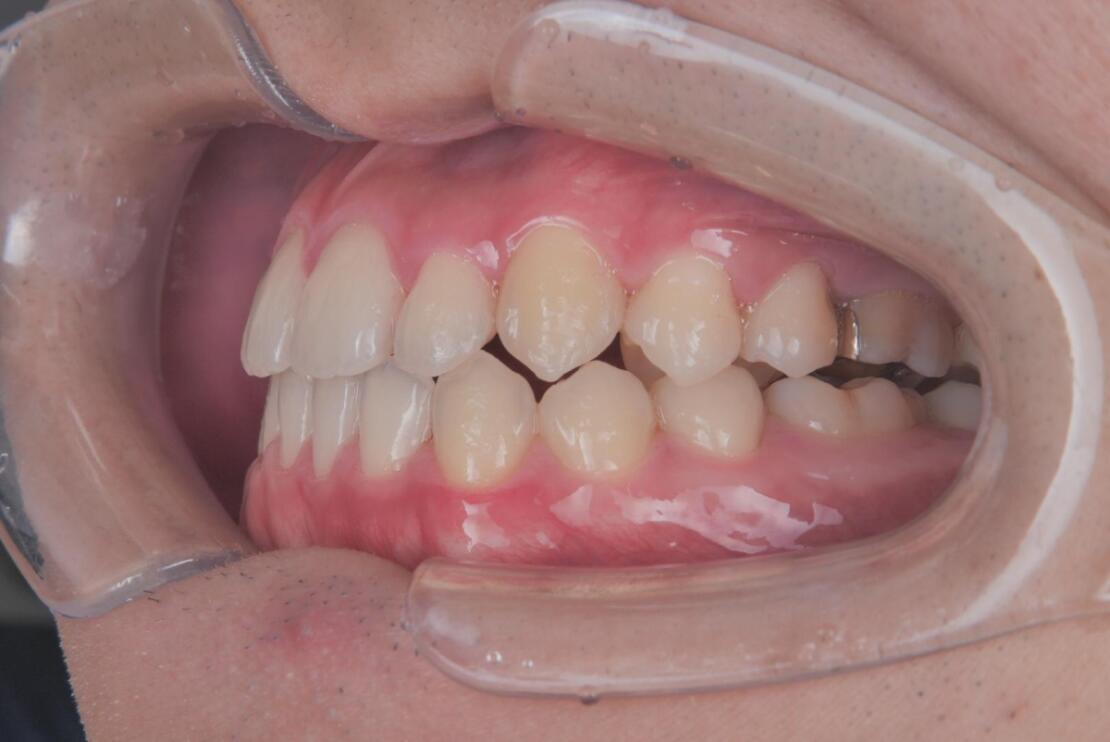

Before 1

Before 2